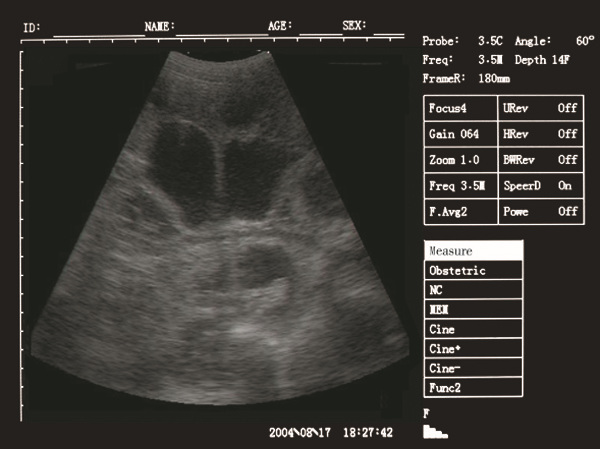

Palm Ultrasound ScannerSU-V5(ultrasonic,black white,Imaging System)

-Full digital imaging technology, crystal-clear Image

Palm Ultrasound ScannerSU-V5(ultrasonic,black white,Imaging System) Images |